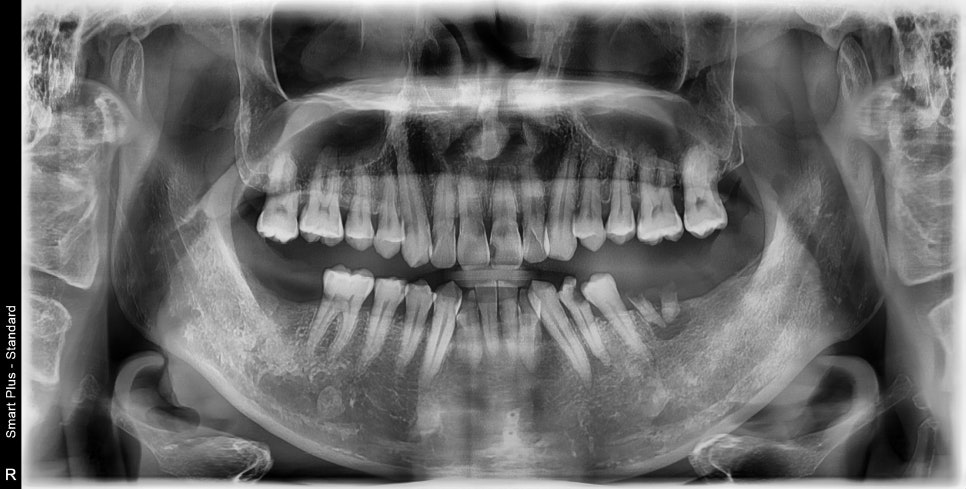

상실된 어금니 부위는 임플란트가 필요하고 해당 부위

말고도 앞니 쪽으로 다발성 우식이 생긴 상태고, 부위에 따라서 신경치료의 가능성이 큰 치아들도 보입니다.

치아의 상실 기간이 길어지게 되면 반대편 치아들이 정출되고

임플란트 식립 후 과거의 이상적인 교합을 만들어 주기 위해서는 의도적으로 크라운 치료를 해야 하며

치아의 정출 양에 따라서 신경치료도 동반해야 하는 경우가 생깁니다.